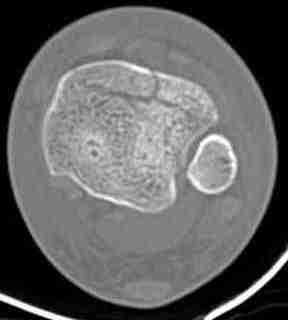

КТ пилона имеем.

При высокоскоростных переломах редко можно встретить изолированную травму пилона, и в моей практике изолированные травмы большая редкость, поэтому, как дополнение к обсуждаемой теме, решил представить свежий, двухдневной давности случай.

Предыдущей сменой до 4:00 утра по поводу открытого перелома бедра, тибиал плато, пилон и надколенника сделана операция.

Пострадавшему 21 г., травма скоростная, после I&D с расширением раны, на бедре сделана операция ретроградным интрамедуллярным штифтом, остеосинтез с частичной резекцией надколенника и ушивание собственной связки.